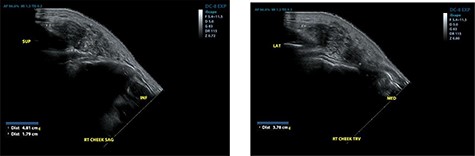

He re-presented 2 years later with a larger 5.0 × 5.0 cm swelling in the same area of the right check (Fig. 3). Ultrasound evaluation demonstrated a 4.8 × 3.8 × 1.8 cm mass with similar features to his previous study (Fig. 4). Blood studies on this occasion showed a leucocytosis with an elevated eosinophil rate of 27.8%. A diagnosis of recurrent KD was made, and this was confirmed on histopathological examination of the re-excised tissue, which again showed involved margins (Fig. 2). The patient was advised to undergo radiation therapy but he refused.

Ultrasound examination demonstrating a heterogenous lesion measuring 4.8 × 3.8 × 1.8 cm mass.